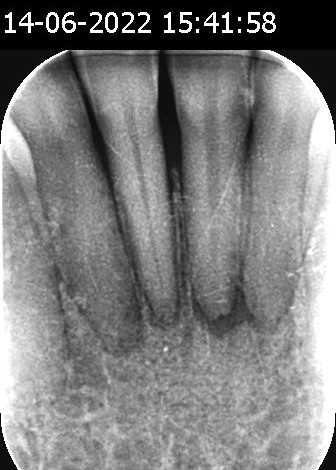

Eine 57-jährige Frau aus Gelderland stellte sich mit lockeren Schneidezähnen (3.2, 3.1, 4.1 und 4.2) vor, die Anzeichen einer Wurzelspitzenentzündung und Kieferknochenresorption zeigten (Diagnose gestellt am 21. Juni 2023). Der behandelnde Zahnarzt in Wageningen empfahl vier Wurzelkanalbehandlungen zur Problemlösung.

Nach einer Reihe von Healozon-Behandlungen berichtete die Patientin jedoch keine Beschwerden mehr. Die zunächst lockeren Zähne sind wieder fest im Kiefer verankert. Röntgenaufnahmen vom 15. Oktober 2024 zeigen eine deutliche Heilung des Kieferknochens und eine verbesserte Zahnknochendichte.

Vorher Nachher